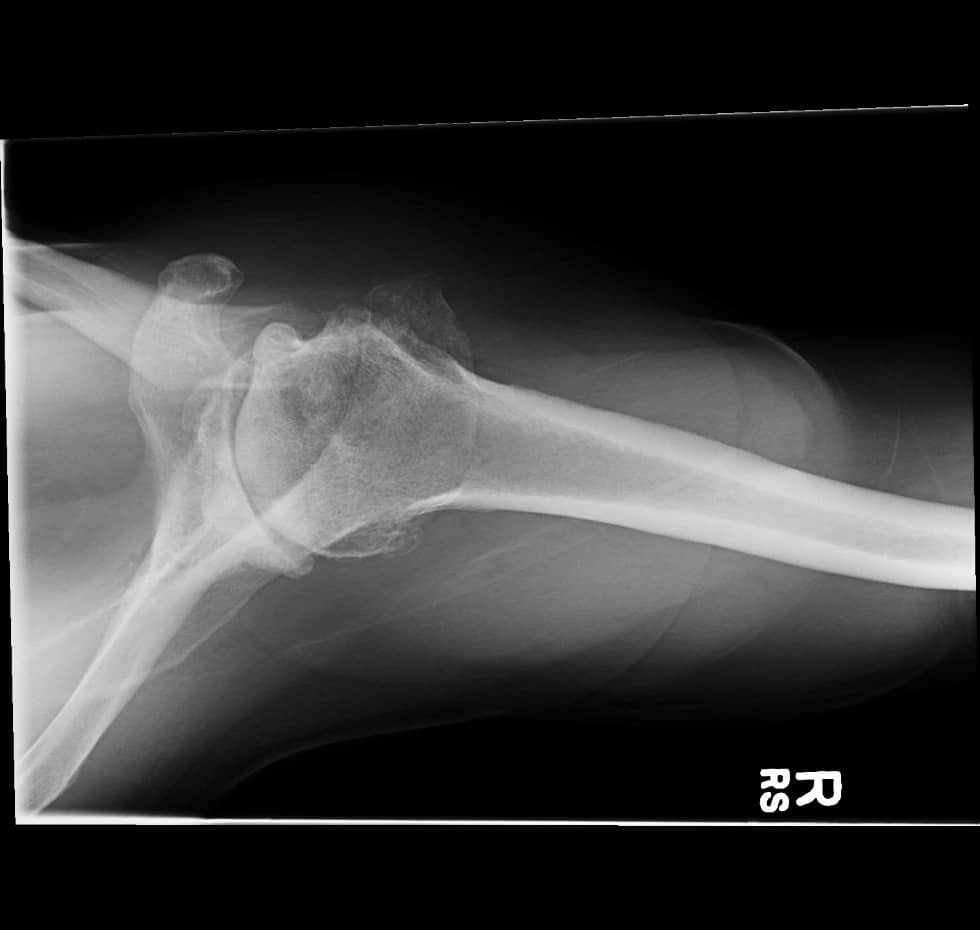

Pre-operative AP and axillary radiographs reveal severe narrowing of the glenohumeral joint space and subchondral sclerosis